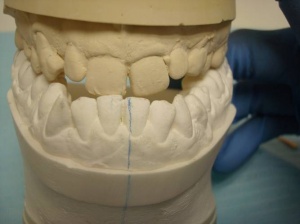

Elle est prognathe avec absence sur l'arcade de 13 et 23.

- La 14 a pris la place de la 13

- La 24 en rotation est couronnée et comble l'espace laissé par la 23.

Le groupe incisivo-canin est en inocclusion.

Madame M. présente une classe III où la rétromaxillie prédomine et son désir est d'avoir selon ses termes: "des dents du haut alignées et qui ne partent pas dans tous les sens".

Nous proposons à notre patiente de prendre des empreintes et de faire appel au talent de notre prothésiste Claude Valtin (Paris) pour réaliser une étude prélable (wax up) en vue de réaliser des facettes et des couronnes tout céramique.

11, 12, 21, 22 : 4 facettes

24 : cette dent est déjà porteuse d'une couronne. Nous réalisons une couronne tout céramique sur un inlay core en or.

14, 15, 25 : couronnes tout céramique sur dents conservées vivantes.